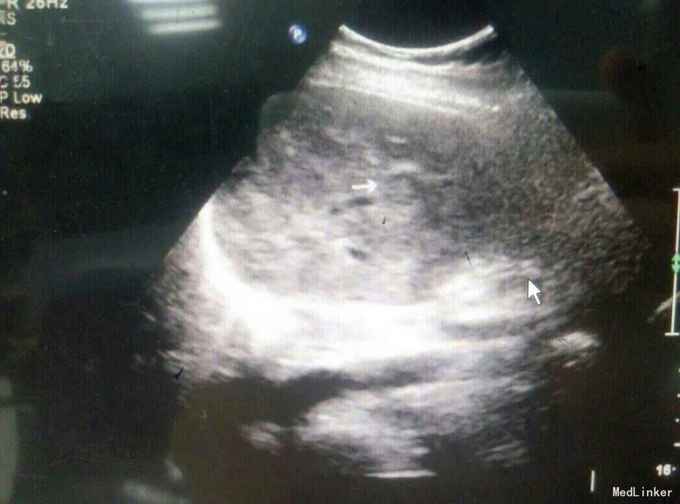

患者,女,43岁,左乳癌术后2年余,发现肝脏占位3天

查体:未及明显异常 辅助检查:腹部彩超发现肝脏多发占位,考虑转移,腹部增强CT:肝脏多发结节,考虑乳腺癌肝转移

随访与讨论:患者入院时肝功能就偏高,也算是一个肝功能受损征相,而且彩超检查发现门静脉有癌栓形成,说明比较晚期,预后不良,所以采取姑息性辅助化疗,希望可以减轻患者病痛。当然同时也要排除其他地方转移,以采取相关治疗措施。